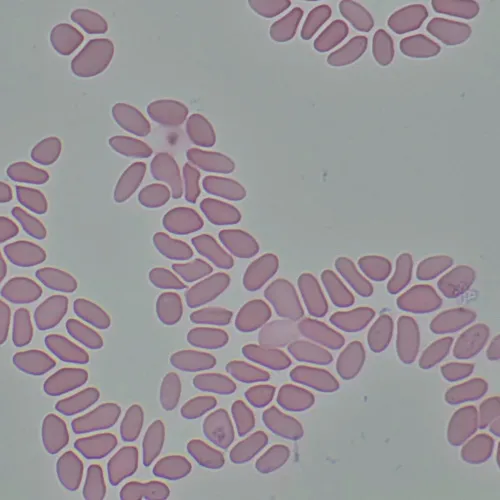

Изследователски клас микроскоп. Конструиран за наблюдение на прозрачни и полупрозрачни биологични проби, като например натривки и напречни сечения в преминаваща светлина по метода на светлото поле. Монтирането на допълнителни принадлежности ще осигури възможност за използване на методите на тъмното поле, фазовия контраст, диференциалния интерферентен контраст, флуоресценцията и поляризацията.

Микроскопът е подходящ за микробиологичен анализ, медицински диагностики и решаване на научни и изследователски проблеми.

- Наблюдение на прозрачни и полупрозрачни образци по метода на светлото поле с пропусната светлина